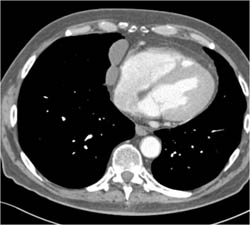

Normal LAD and Circumflex in 3D